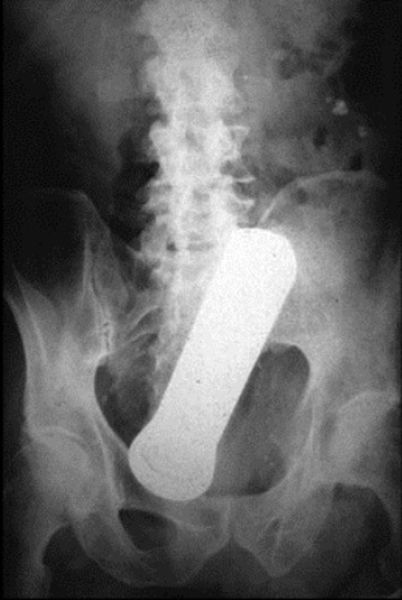

Flashlight